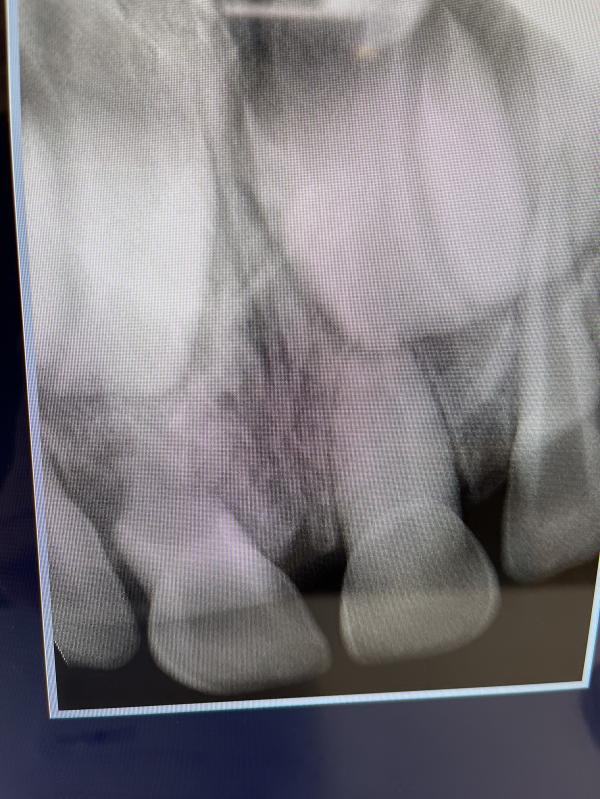

У дочки свищ на десне, пол года назад ударилась губкой(( стоматолог сказал зуб удалять. Я в панике- как удалять зуб 2х летнему ребёнку? Под общим наркозом?? У кого есть опыт? Может проверенные места и врач? Пока вот по отзывам тут хвалят рудент и фэнтези

У нас был свищ в 4.9.удаляли с уколом анестезии.так как это молочный зуб, его удаляют.лечат только коренные